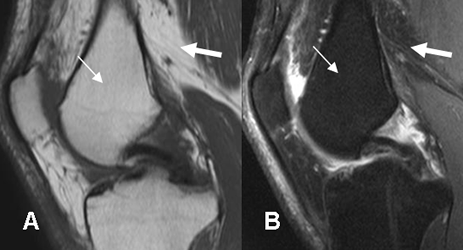

Fig 7. Medula ósea en adulto normal

A: RM sagital en T1 y B: RM sagital en STIR. La señal de la medula osea amarilla (Flecha delgada), es similar a la de la grasa (Flecha gruesa).